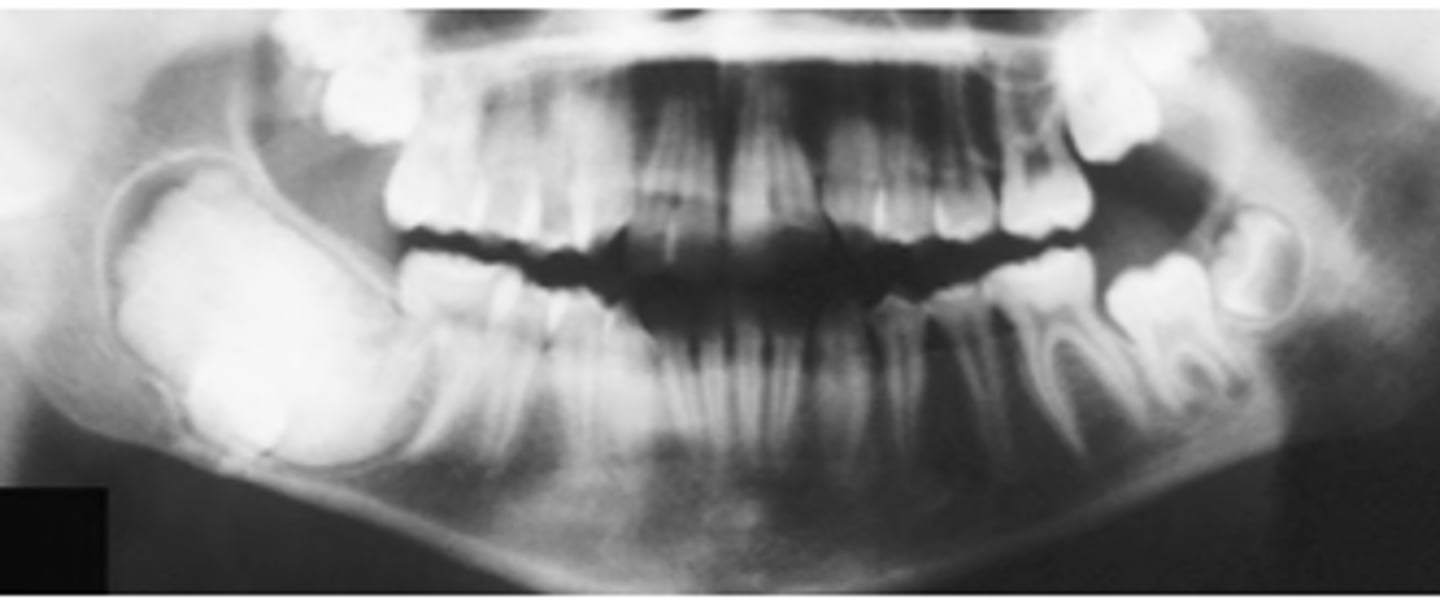

What are radiographic features of ameloblastic fibromas?

⢠unilocular/multilocular radiolucency

⢠usually associated with unerupted tooth (75%)

What are radiographic features of ameloblastic fibro-odontomas?

⢠well-defined radiolucency + radiopaque component

*small fleck to large calcified masses